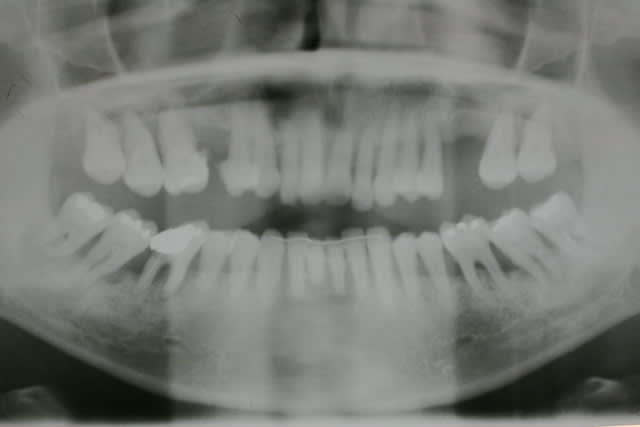

mais comment tu fais pour bosser avec des pano aussi dégueulasses ?

tu devrais investir, je ne doute pas que tu saches interpréter des panos mais quand même, c'est du confort pour bosser. pourquoi s'en priver?

Pfs les patients arrivent avec leur pano de chez leur praticien

Il y en une bien floue ds la bande mais bon comme 1er doc avant les scanners ça peut déjà donner une idée